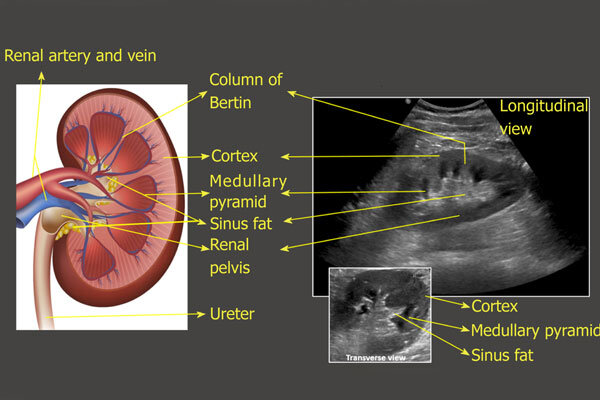

رادیولوژی